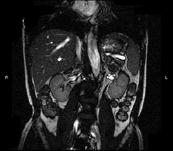

问题 男,52岁,下肢无力伴多饮多尿2 年余,实验室检查:低血钾,血醛固酮水平及24h 尿醛固酮定量超过正常值,MRI检查如图所示,应诊断为 ( )

选项 A、左肾上腺髓脂瘤 B、左肾上腺转移瘤 C、左肾上腺腺瘤 D、左肾上腺嗜铬细胞瘤 E、左肾上腺囊肿

答案 C